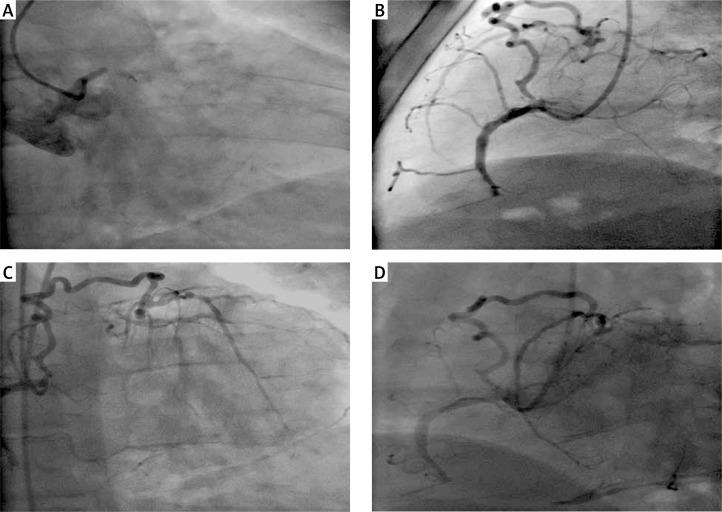

Alhejily Wesam A

Department of Medicine, King Abdullaziz University, Jeddah, Saudi Arabia.

Postepy Kardiol Interwencyjnej. 2015;11(3):244-5. doi: 10.5114/pwki.2015.54023. Epub 2015 Sep 28.